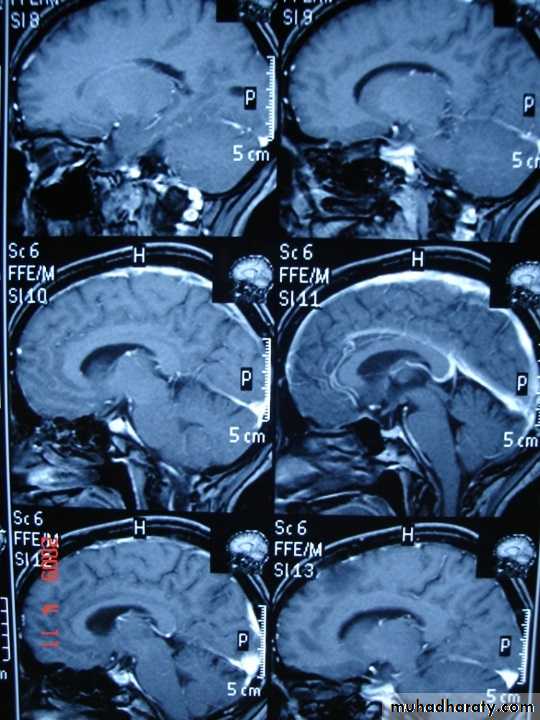

- the most characteristic appearance is that of peri ventricular nodular Hyper intense lesions on T2 weighted images.

-the plaques are also well seen at the gray- white matter interfaces.

-some lesion may show a central area of greater signal intensity , resembling a target.

-contrast enhancement after giving gadolinium occurs in the acute phase indicating activity & in the chronic phase doesn't enhance.

SAGITAL FLUID ATTENUATION INVERSION RECOVERY SEQUENCE: OVOID PLAQUES ( HIGH SIGNAL INTENSITY) , WHICH ARE PERPENDICULAR TO LATERAL VENTRICLE.